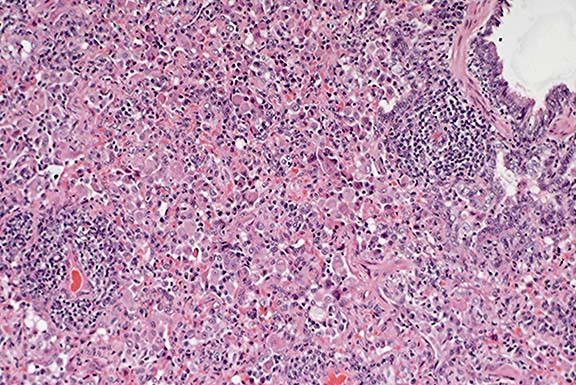

Case 9-2a. Neoplastic mast cells expand the sinusoids between necrotic hepatocytes (right). 40X

Case 9-2b. The mast cells contain sparse to numerous reddish-purple (metachromatic) granules in the cytoplasm. Giemsa. 40X

AFIP Diagnoses: 1. Liver: Mast cell tumor, malignant, Domestic Shorthair cat, feline. 2. Liver: Necrosis, coagulative, centrilobular, diffuse.

Conference Note: Although this feline lesion is often called mastocytosis, the diagnosis of malignant mast cell tumor was preferred because the term mastocytosis does not clearly indicate that the condition is neoplastic.